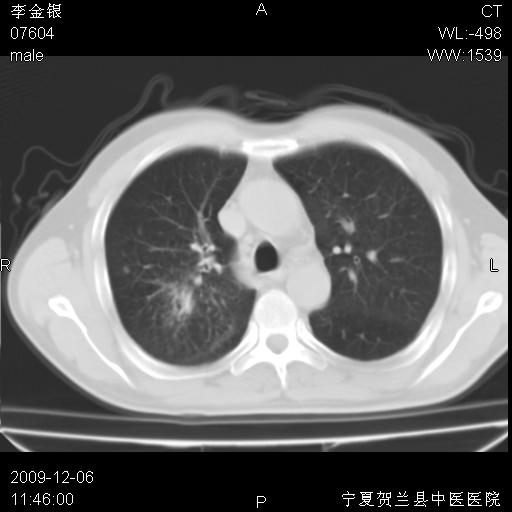

该病人 ,男,62岁,主因咳痰带血两天

支持右侧中央型肺癌伴上叶阻塞性炎症.

考虑右肺中心型肺癌伴阻塞性肺炎及右肺门淋巴结转移,建议纤维支气管镜进一步检查。

右肺上叶后段支气管阻塞,右上肺门占位,相应肺段阻塞性肺炎,右肺门有淋巴结肿大。诊断右肺上叶中心型肺癌,阻塞性肺肺炎、右肺门淋巴结转移。

右上叶支气管狭窄,管壁增厚,远端斑片状软组织影,病灶邻近叶间裂,叶间裂无移位。

诊断右肺中央型肺癌。

那个片影应该大部分都是病灶,病灶沿肺段支气管分支生长,后段完全显示不清、闭塞。若为不张应该伴有叶裂的移位,若为炎症应有空气支气管征。

考虑右侧中央型肺癌伴右肺上叶后段阻塞性炎症、肺不张、右肺门和纵隔淋巴结肿大。